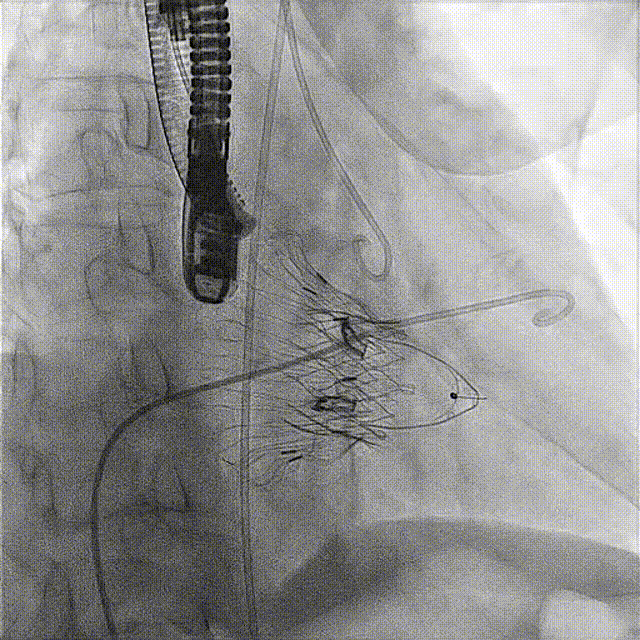

術(shù)后DSA

術(shù)前經(jīng)過(guò)全面系統(tǒng)的評(píng)估后,考慮患者存在高齡、心功能減低、三尖瓣瓣環(huán)重度擴(kuò)張(三尖瓣極重度反流)等高危因素,因此廈心結(jié)構(gòu)心團(tuán)隊(duì)聯(lián)合超聲心動(dòng)、麻醉及護(hù)理團(tuán)隊(duì),制定了詳盡的圍術(shù)期治療方案及術(shù)中治療難點(diǎn)預(yù)案。術(shù)中,由王焱院長(zhǎng)主刀,在蘇茂龍主任超聲心動(dòng)團(tuán)隊(duì)的輔助,上海市第一人民醫(yī)院陸方林主任的協(xié)助下,僅用時(shí)30分鐘,即順利完成了三尖瓣原位置換的手術(shù)。術(shù)中患者血流動(dòng)力學(xué)穩(wěn)定,術(shù)后即刻顯示LuX-Valve Plus瓣膜位置良好,固定穩(wěn)定,瓣膜功能正常,無(wú)瓣周漏。

觀摩手術(shù)的臺(tái)灣專家對(duì)此次手術(shù)過(guò)程及LuX-Valve Plus器械展示出的優(yōu)異性能表示贊譽(yù),表示與傳統(tǒng)外科三尖瓣治療方式相比,LuX-Valve Plus介入三尖瓣治療創(chuàng)傷小,安全性高,手術(shù)時(shí)間短,術(shù)中術(shù)后患者血流動(dòng)力學(xué)可平穩(wěn)過(guò)渡;且與現(xiàn)有的三尖瓣緣對(duì)緣修復(fù)手術(shù)相比,LuX-Valve Plus原位三尖瓣置換對(duì)術(shù)中影像依賴度相對(duì)更低,操作更加便捷,并且憑借獨(dú)特的錨定及瓣葉固定方式可以最大程度的避免高度房室傳導(dǎo)阻滯的發(fā)生,同時(shí)也擁有較為豐富的產(chǎn)品規(guī)格,可以適應(yīng)不同三尖瓣瓣環(huán)擴(kuò)張程度的患者,自適應(yīng)防漏環(huán)還可以有效預(yù)防瓣周漏的發(fā)生,產(chǎn)品的諸多特點(diǎn)讓與會(huì)專家再次對(duì)國(guó)產(chǎn)原創(chuàng)醫(yī)療器械刮目相看,并期望可以早日引入海峽對(duì)岸,讓臺(tái)灣地區(qū)的患者也可以使用到祖國(guó)的原創(chuàng)器械,救治更多的患者。